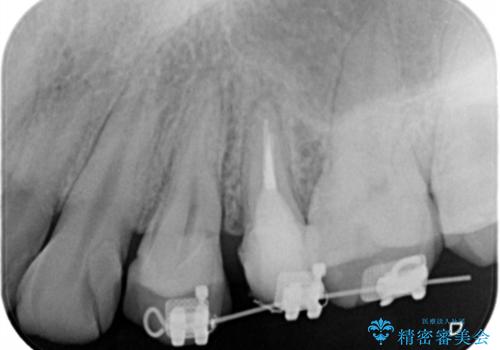

- 歯ぐきの腫れや、歯の内部が黒く見えることからの虫歯の治療を求めて来院されました。

虫歯が大きかったことから、神経の温存はできたものの歯ぐきよりも深い虫歯の問題を解決するため部分矯正治療を併用したセラミック治療を行うこととしました。

当初、歯ぐきよりも深い虫歯のぞんざいや、歯のポジションに問題がありましたがマルチブラケットを用いた部分矯正を行うことで適切な位置へと歯を移動させ、歯周環境を整えたセラミック治療を行うことができました。